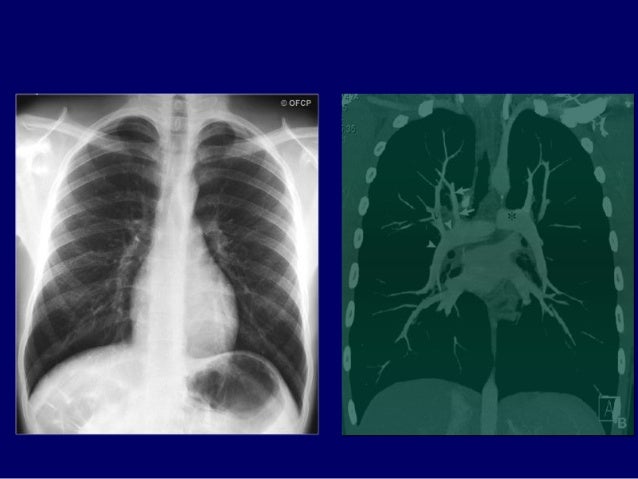

103. 103. TRUNG THẤT GIỮA TĂNG ÁP ĐỘNG MẠCH PHỔI

104. 104. TRUNG THẤT SAU THOÁT VỊ HOÀNH